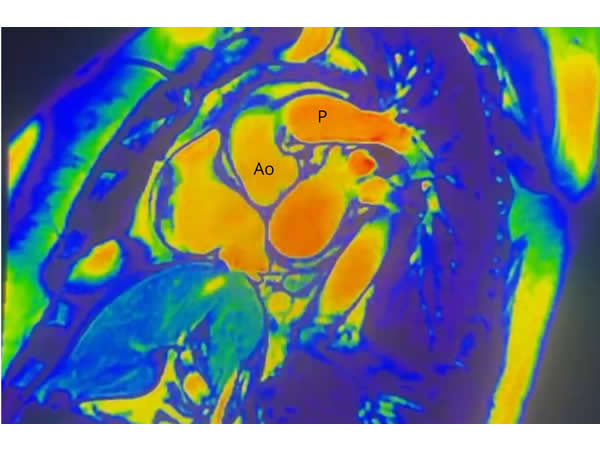

Patología aneurismática de cayado aórtico y aorta descendente torácica en paciente con dolor precordial atípico